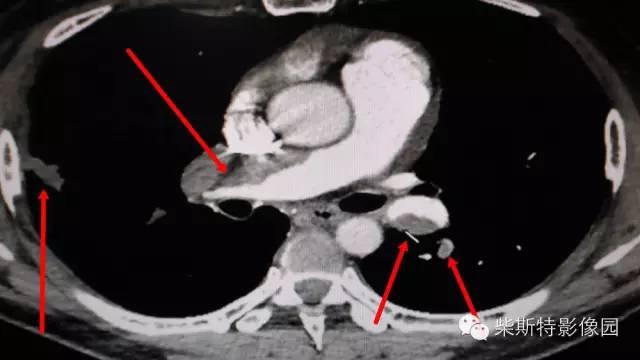

第二大名捕:肺动脉CTA

红色箭头所指处即栓塞导致的充盈缺损,从横断位、冠状位、矢状位三个层面观察,造影剂为高密度白色,而栓子的存在导致造影剂无法充填,从而表现为黑色的低密度影。俗话说的好:长江后浪推前浪!肺动脉CTA的本领已经基本超越其“大哥”肺动脉造影!还可以估测房室大小!